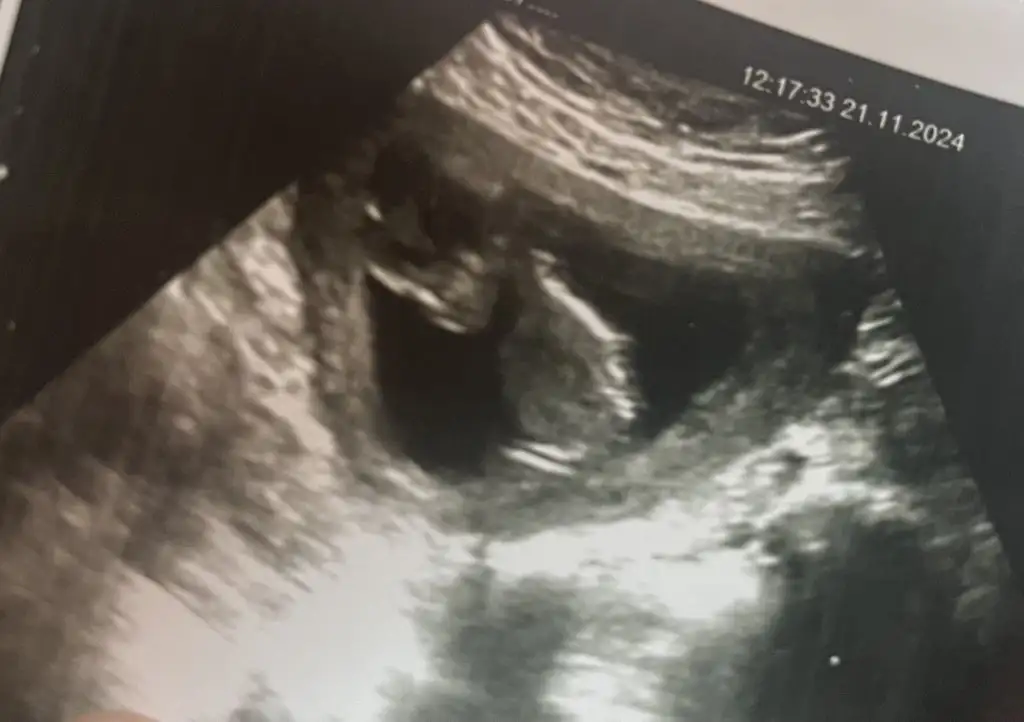

Aradan uzun zaman geçmiş ama banada bakan olabilirmi acaba çok merak ediyorum 23 haftalık karından cekilmis ultrason